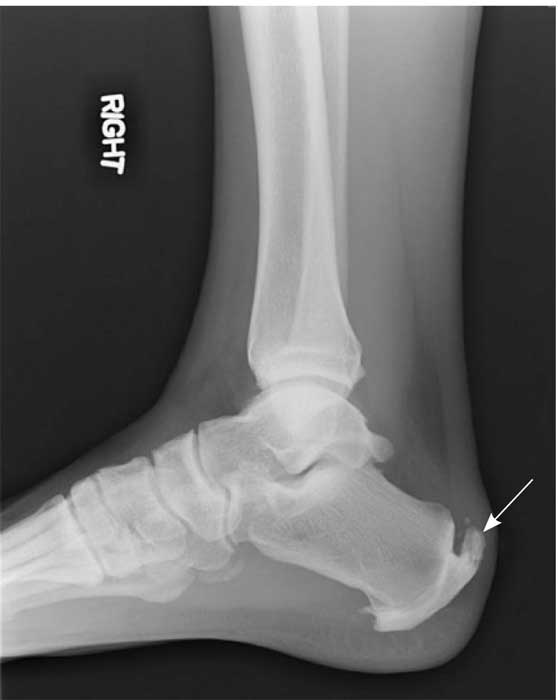

• Стресові переломи.

• Спур (новоутворення) п’яткової кістки.